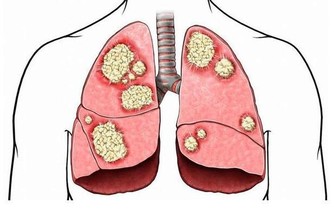

腳面部位本來是平坦無皺紋的,如果表面出錢青筋凸起,說明腳部的血液循環開始出現受阻現象。雖然身體暫時感覺不到其他的不適癥狀,但是我們千萬不可以忽視這一癥狀。往往大病之前總是潛伏著一些小毛病。

腳部出現青筋,說明血液循環不暢通,但是前期人體並不會出現其他不適應的癥狀。沒有出現不適,不代表完全沒問題。血液循環不暢通,將會導致心臟部位無法及時接受身體回流的血液,繼而影響下一輪供血;還會導致腳部功能退化,出現足部組織壞死的現象。

所以,腳部出現青筋一定要引起註意,防患於未然總是疾病最好的對手。